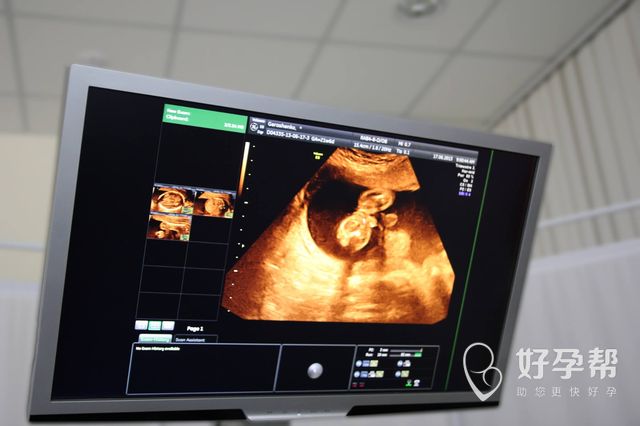

郑州有没有技术比较好的试管医院呢?已经付出了很大的努力,却仍然没有怀上孩子,实在没有办法才会选择试管的方式,越来越多夫妇都有着这样的情况了。为什么会出现不孕不育问题呢?引起这种情况的因素很多,问题已经存在了,继续苦恼也没有任何意义,所以尽快找到专业的医院进行手术,才会知道是否有着做父母的可能性,想要知道具体是怎么回事,就可以看一看下面关于郑州哪个医院做试管婴儿最好的介绍了。

现在很多夫妇都会在当地做试管手术,因为国内的试管水平已经很平均了,并不会有太大的差距,而试管手术的费用也不算低,所以不用出远门做手术,除了更加方便之外,也能够节省更多的费用,当然会成为较多人的理想选择。对于郑州哪个医院掌握着先进并且可靠的试管技术,大家都会有着较高的关注度,妇幼保健院、郑大一附院、人民医院、郑州大学二附院等,都值得大家进行更多了解。

2、郑州哪个医院做试管婴儿会成功呢

试管手术需要满足较多的条件,才能够成功,除此以外,也会受到较多因素的影响,从这些方面,就可以知道试管失败率确实很高了,而郑州哪个医院做试管婴儿最好呢?之前已经说到了一些比较知名,并且技术也很先进的医院,那么接下来当然就要看一看如何会有更高的成功率了。不论是哪家医院,只要年龄越小,身体素质越好,以及卵子质量越高,就是更易成功的一些条件了。

3、郑州哪个医院有三代技术

现在试管技术已经更加进步了,如果还在选择一代或是二代技术,确实会有着一些无法避免的问题,当然也不是朋友们的理想选择。可以尝试三代手术的话,相信大家也会更加放心,上面提到的医院,都掌握着三代技术,朋友们能够进行更多询问。

了解到这里之后,关于郑州哪个医院做试管婴儿最好?以及三代技术怎么样,认真看过介绍内容的朋友,都可以知道答案到底是什么了。三代之所以更受欢迎,就是由于能够保证试管宝宝更健康,有遗传病基因也能被检测出来,优势当然非常多。